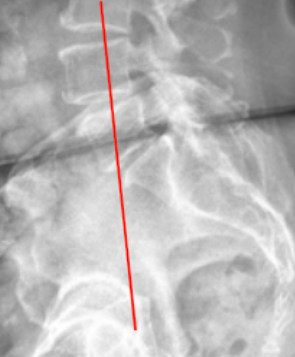

lumbar lordosis

Segmental Lordosis

George’s Line (Posterior Vertebral Body Line)